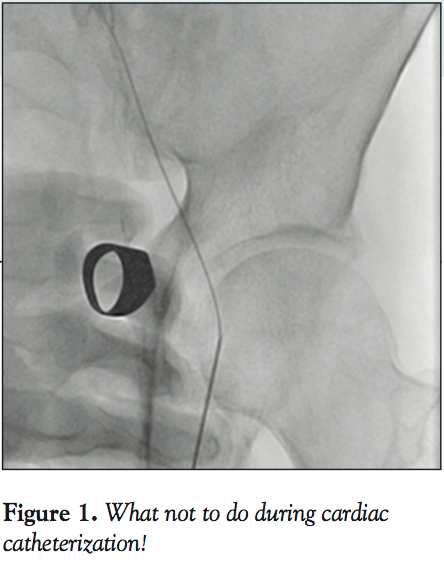

I frequently visit various cardiac catheterization laboratories both in the US and abroad and watch live cases at various interventional meetings. I find such experiences invaluable for “opening the mind” to new, different, and often better ways to do what we do every day. However, there is one aspect of the catheterization procedures that I often find discomforting: radiation safety practices vary widely and are often ignored. I recently observed an expert interventionalist skillfully complete two extremely challenging peripheral interventions. In both cases, his hands were in the middle of the radiation beam for several minutes (Figure 1)! The response to my pleas about this was: “I did not like it, but I had to do it.”

How can interventionalists reduce radiation exposure? The simplest first step is to not step on the fluoroscopy pedal when not looking at the screen. Although this appears self-evident, I remain amazed at how often this simple principle is ignored! Another obvious second step is to not insert our hands in the radiation field. Of course there are exceptions — occasionally in an arresting patient undergoing emergency PCI the hands of the person performing cardiac compressions may get in the beam — but this should be the exception, rather than the rule.